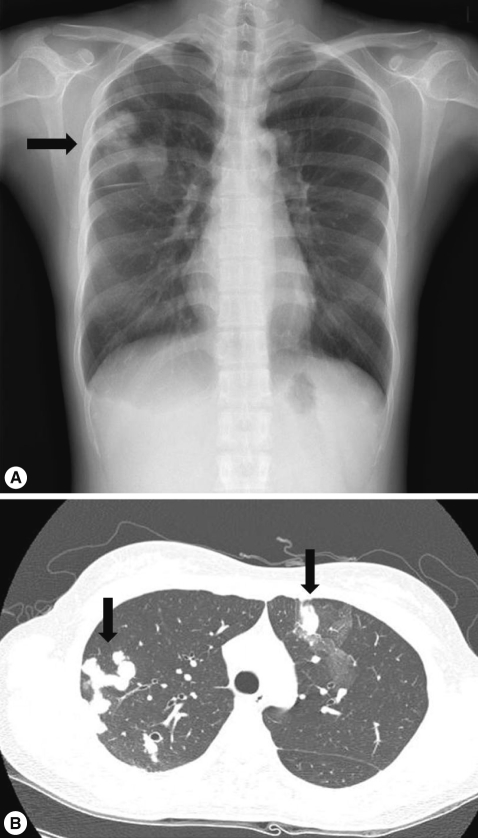

3. Serum tumor markers showed a high CA 125 level of 47.6 U/ml (normal <35 U/ml). Other laboratory tests revealed no abnormal findings. A chest X-ray showed multiple mass-like opacities in the right lung (

Fig. 1A). Chest CT revealed multiple nodules with adjacent areas of ground-glass opacity (GGO), which corresponded to hemorrhagic infarcts as in a case of hemorrhagic metastasis or other benign conditions (

Fig. 1B). FDG-PET CT was performed to find out a possible primary site of malignancy. However, it revealed no remarkable abnormal finding except an increased FDG uptake (max SUV: 3.1) in the lung lesions (

Fig. 1Chest X-ray and computed tomography (CT) on admission. (A) Multiple mass-like opacities are shown in the right lung (arrow). (B) Multiple nodules with adjacent areas of GGO, suggestive of hemorrhagic metastasis are observed in both lungs (arrows).